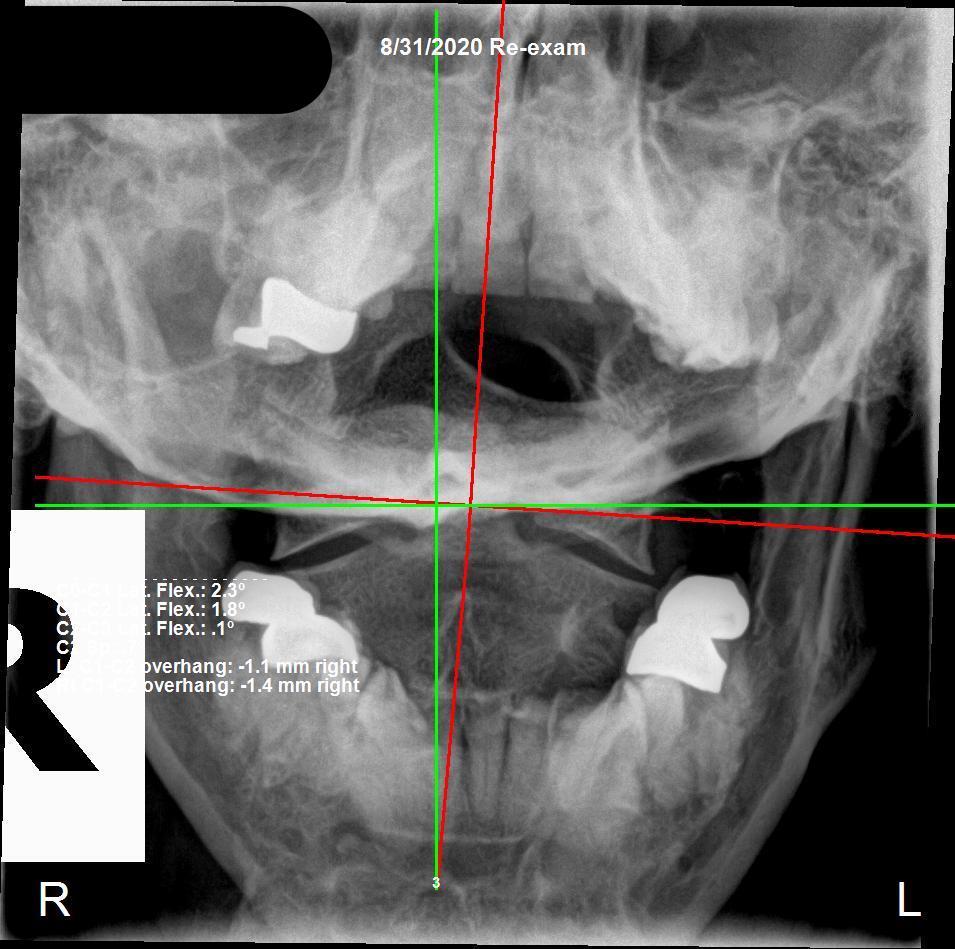

Spinal X-Ray showing subluxation — Rochet Family Chiropractic Royal Palm Beach FL

As is customary in our office, we took X-rays to establish a baseline. The results revealed what years of non-specific care had left behind. To his surprise, his neck was nowhere near where it was supposed to be. He couldn't believe he was in such spinal misalignment after being under care for so many years. At his previous office, he received the same adjustment every two weeks — both sides of his neck, three in his mid-back, and both sides of his low back and pelvis. What chiropractors call "The Miracle 7." The major problem: there is no specificity, no purpose to the action.